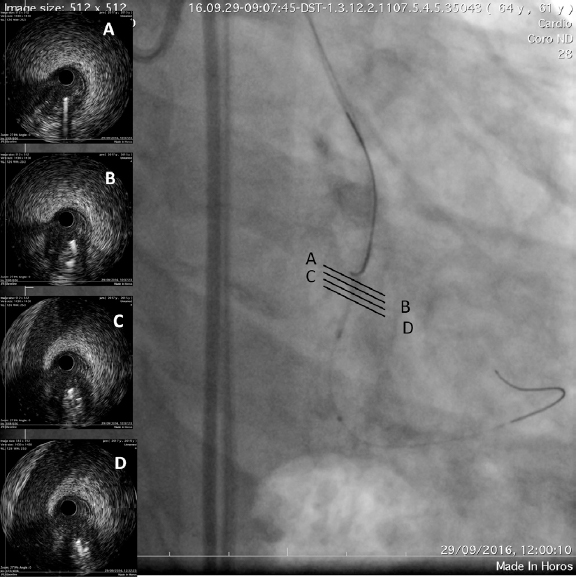

The intravascular ultrasound (IVUS) is useful when the entry site is ambiguous and there are no references to position the guidewire. A lateral branch is required to place the guidewire and IVUS. In these cases, the Slipstream technique38 is very useful. It consists in placing a dual-lumen micro-catheter (DLM) behind the IVUS above the branch guidewire. This increases tremendously the strength exerted with the guidewire that exits the DML lateral port providing better torque and grip (figure 3). The IVUS shows where the occlusion of the vessel is in order to navigate the guidewire (of high-gram, directivity, and torque-response) towards that point (figure 4).

Figure 3. The occluded vessel is at the 6 o’clock position approximately (A) as the guidewire is moving towards the occlusion (B, C and D).

Figure 4. The catheter of intravascular ultrasound in the subintimal space is between the 9 and 12 o’clock positions and true lumen between the 3 and 9 o’clock positions.